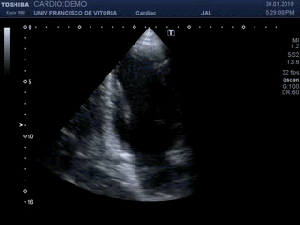

139. Ecocardiografía. Estudio Paraesternal Eje Largo.